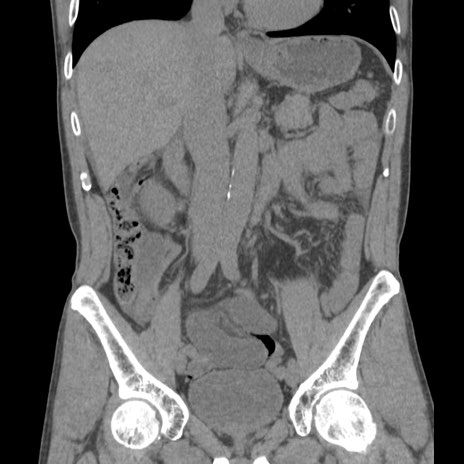

症例56 CT(冠状断像)

横断像